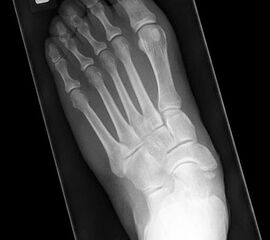

Stehende Aufnahmen des Fußes dorsoplantar (dp) und seitlich sowie des OSG anteroposterior (ap) sind die Grundlage der konventionellen Röntgendiagnostik (Abb. 5). Ergänzend werden gelegentlich die Rückfuβ-Alignement Aufnahme nach Saltzman 19 und Vergleichsaufnahmen der Gegenseite durchgeführt.

Der Talo-Metatarsale I Winkel bzw. die laterale talonaviculare Subluxation auf der stehenden dorsoplantaren Aufnahme des Fuβes dokumentieren das Ausmaβ des Vorfuβ abductus (Abb. 6 a,b). Ein dp Talo-Metatarsale I Winkel von > 10° (nach medial konvex) ist als pathologisch anzusehen. Mit der Bestimmung der talocalcanearen Divergenz (Abb. 6 c) erhält man ein Eindruck über das Ausmaβ des Rückfuβ valgus; eine leichte Divergenz bis ca. 12° gilt als physiologisch 20.

Auf der seitlichen, stehenden Aufnahme des Fußes wird ebenfalls der laterale Talo-Metatarsale I Winkel (Abb. 6 d) gemessen und so das kollabierte mediale Längsgewölbe dokumentiert. Auch hier gilt ein Talo-Metatarsale I Winkel von > 5° (nach plantar konvex) als pathologisch 21. Der Kollaps findet dabei meist im Talonaviculargelenk, seltener in der Naviculocuneiform-Gelenkreihe statt. Instabilität und Arthrose im 1. TMT sollten ausgeschlossen oder bei der Operationsplanung mit einbezogen werden. Weitere wichtige radiologische Messungen zur Beurteilung der Planovalgus-Statik und Progression der Deformität sind der laterale talo-calcaneare Winkel (Abb. 6 e) und der Abstand des Os cuneiforme-Unterrandes zum Untergrund (Abb. 6 f, Cuneiform height, 22. Eine anteriore Translation des Talus auf dem Kalkaneus findet man sowohl auf der ap, als auch auf der seitlichen Aufnahme des Fuβes mit Aufhebung der Cima-Linie.